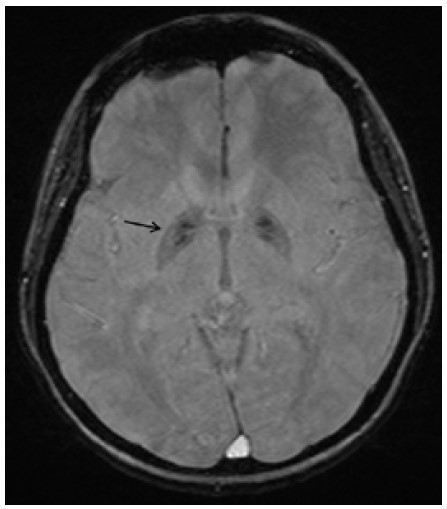

Ультразвуковое исследование органов шеи выявило увеличение размеров щитовидной железы. Ниже левой доли щитовидной железы присутствовало узловое образование (0,8 см) со значительно сниженной эхогенностью [Рис. 1]. МРТ головного мозга продемонстрировала двустороннюю кальцификацию бледного шара с симметричными гиперинтенсивными включениями на Т1- и Т2-взвешенных изображениях [Рис. 2], а также гипоинтенсивность на взвешенных по магнитной восприимчивости изображениях (SWI) [Рис. 3]. Селлярные/супраселлярные поражения либо усиления отсутствовали. Для подтверждения аутоиммунной этиологии мы провели анализ периферической крови пациентки на содержание CD4+FOXP3+Treg клеток, которое составило 2,47 при нормальном значении 6,68, что свидетельствует в пользу аутоиммунной этиологии заболевания.

Рис. 3: Аксиальное взвешенное по магнитной восприимчивости изображение (TR-49/TE/40/угол переворота 15°) демонстрирует двустороннюю гипоинтенсивность бледного шара (стрелка), что свидетельствует о кальцификации базальных ганглиев.

У данной пациентки наблюдалось сочетание необычных патологических состояний в дополнение к аутоиммунному тиреотоксикозу. У пациентки присутствовала аутоиммунная гемолитическая анемия ‑ известное, хотя и редкое, сопутствующее состояние при болезни Грейвса. Также у неё присутствовала кальцификация глубоких структур серого вещества головного мозга в сочетании с узловым образованием паращитовидной железы на фоне нормального содержания кальция и нормального уровня ПТГ.

Неожиданной находкой в настоящем случае было узловое образование в области предполагаемой локализации паращитовидной железы, ниже левой доли щитовидной железы; образование было выявлено при ультразвуковом обследовании в связи с гиперплазией, аденомой либо инфильтрацией паращитовидной железы. Оно было расположено отдельно от нижнего края щитовидной железы и не являлось экзофитным узловым образованием щитовидной железы. Также было возможно, что узловое образование представляет собой лимфатический узел небольшого размера. Возможность для подтверждения паратиреоидного генеза узлового образования по поглощению сестамиби отсутствовала в связи с недоступностью оборудования для проведения сцинтиграфии паращитовидных желез с сестамиби. Тем не менее, на МРТ пациентки присутствовали признаки кальцификации базальных ганглиев. У пациентки отсутствовали хронические заболевания печени, а также признаки метаболических либо нейродегенеративных расстройств. Наиболее вероятной причиной развития кальцификации базальных ганглиев является эндокринная патология, вызвавшая нарушение метаболизма кальция; данная ситуация может напрямую быть связанной с тиреотоксикозом либо развиваться вторично, на фоне патологии паращитовидной железы [4,5].